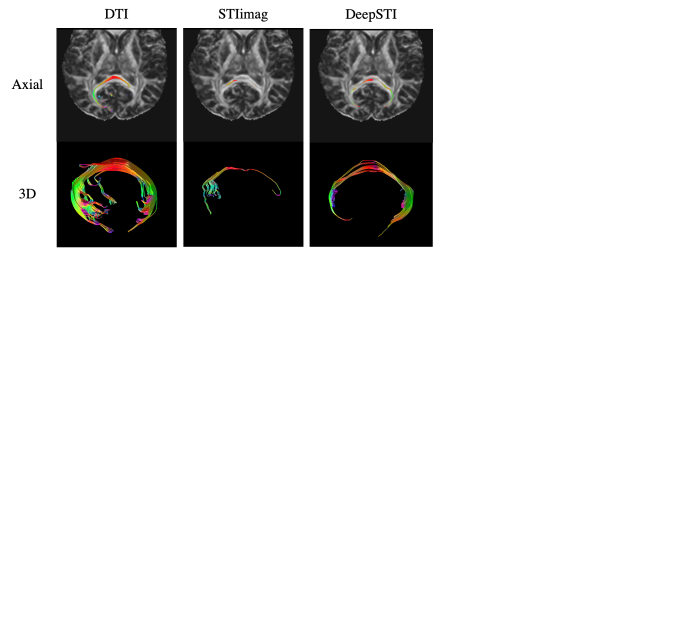

Refer to caption

Figure 6: Tracking of callosal fiber bundle that connects the occipital lobes via the splenium of corpus callosum (forceps major) from measurements of a subject at 7T with 0.98×\times0.98×1(mm)3absent1superscript𝑚𝑚3\times 1(mm)^{3} resolution. From left to right: reference DTI reconstruction (acquired at 2.2 mm isotropic resolution and interpolated to 0.98×\times0.98×1(mm)3absent1superscript𝑚𝑚3\times 1(mm)^{3} resolution), STI reconstruction from STIimag using four orientations, STI reconstruction from DeepSTI using four orientations. Note that MMSR, aSTI and aSTI+ did not recover any tracts that satisfy the anatomical constraint of the forceps major.

Fig. 6 depicts tractography results for the forceps major using the same 7T dataset as in Fig. 5. In this task, most existing STI methods (including MMSR, aSTI and aSTI+) failed to reconstruct the forceps major, yielding no tracts that satisfy the given anatomical constraint. STIimag was able to produce a small portion of tracts, but largely incomplete. DeepSTI yielded the most coherent and complete result among all STI methods, with a complete C-shape structure.